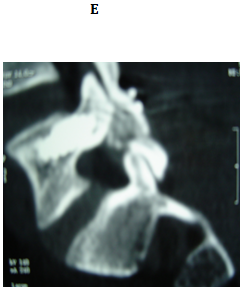

No implant failure was detected in the follow up radiographs. At the final follow up, radiological healing could be achieved bilaterally in all patients (86.6%) but four. Three of them had initial defects >3mm and one from 2-3mm, all at L5. For the healed cases, the mean time to union was 4.7 months. In the cases which did not heal, only 1 complained of significant back pain at final follow up. The other 3 did not complain of pain at final follow up (Figures 3 & 4).

Figure 3 18 years old male with bilateral pars defect at L5 underwent the procedure. (A) Preoperative lateral plain radiograph showing the defect (B) Preoperative MRI shows intact intervening disc (C, D) Immediately postoperative plain radiographs (E) CT 1 month later. Note the bone graft incorporating at the defect site.